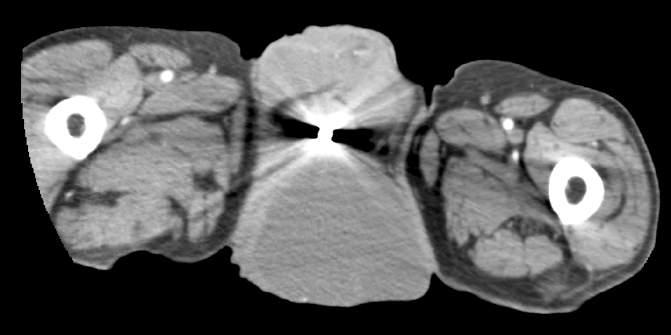

Issuu converts static files into: digital portfolios, online yearbooks, online catalogs, digital photo albums and more. Sign up and create your flipbook.